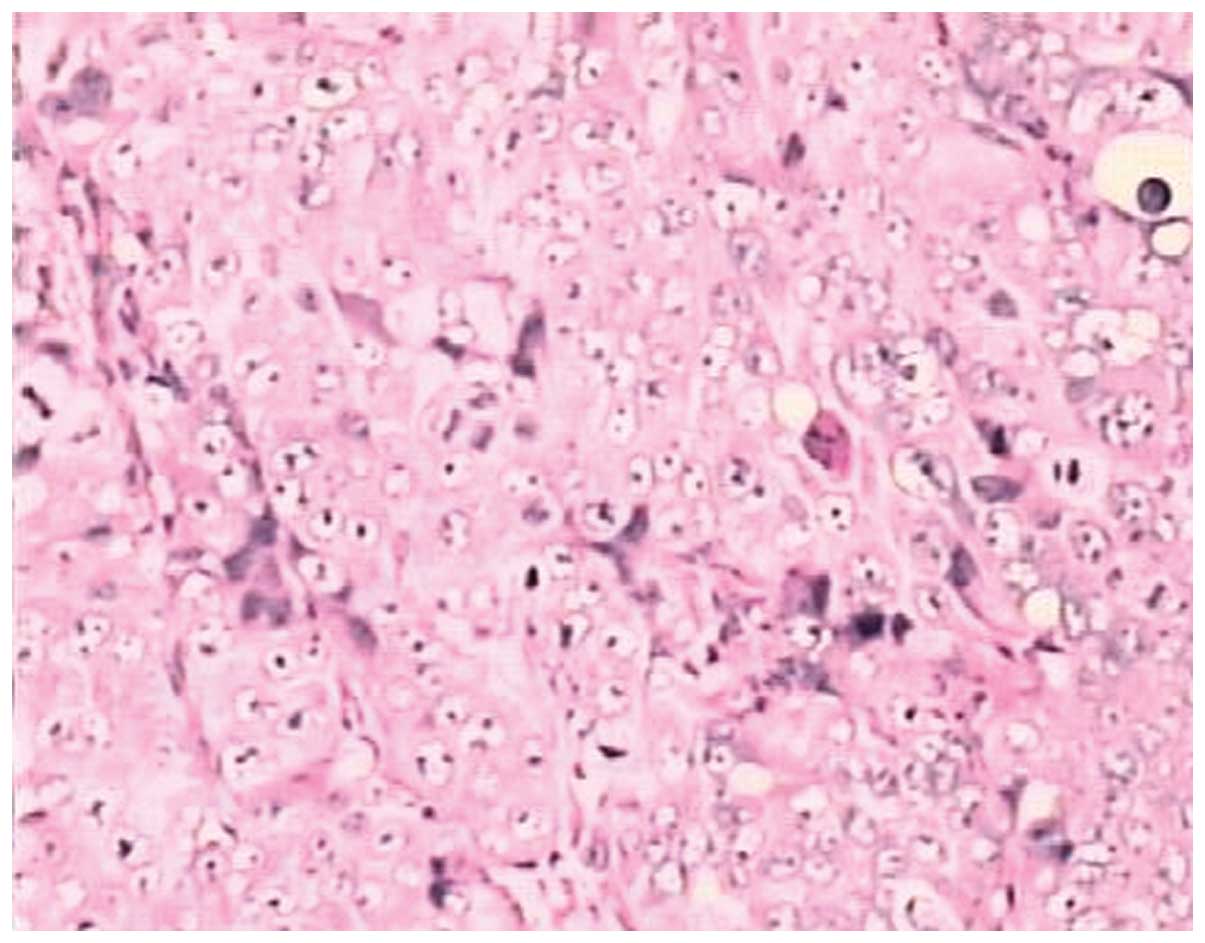

Fourteen days after the subcutaneous inoculation, all 35 nude mice with an observed tumor growth survived with a balanced diet. According to the standards of cancer-bearing models, 30 mice were chosen for further experiments. The mice were sacrificed and their tumor tissues were excised for pathological examination using H&E staining. The morphologies of the model and human endometrial adenocarcinoma tissues were identical. Thus, the validity of the nude mice model of human endometrial adenocarcinoma was confirmed (Figs. 5 and 6).

Pathological features of the transplant from a nude mouse (Magnification, x200).

The model involving nude mice with endometrial adenocarcinoma xenografts was successfully established. The validity of the model was confirmed by the observation that the pathological morphology of the model and that of the human endometrial adenocarcinoma tissue were identical. Pathological karyokinesis was observed in the endometrial adenocarcinoma tissue with a densely stained nucleus using a light microscope. An immunohistochemical assay was used to evaluate the expression of COX-2 and the MVD. The results indicated that the expression level of COX-2 and the MVD were attenuated by celecoxib in a concentration-dependent manner. Statistical significance was observed in the COX-2 expression level and MVD between the test group and the control group (P<0.05 and P<0.01 respectively). The expression level of COX-2 positively correlated with MVD (r=0.921, P<0.01).